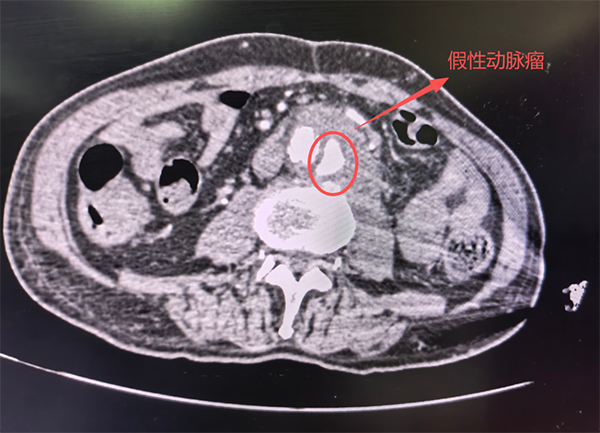

“当务之急是解决结肠扩张积便问题,排除肠道问题对影像检查的干扰。”普外科会诊后,虽经灌肠处理,患者腹痛有所减轻,但恶心呕吐依旧。复查腹部增强CT发现:腹主动脉下段周围见团块状软组织密度影,最大截面约5cm*2.9cm,病灶竟然“包绕”了腹主动脉!“罪魁祸首”浮出水面:腹主动脉下段破裂出血假性动脉瘤形成!立即联系介入科!

术前